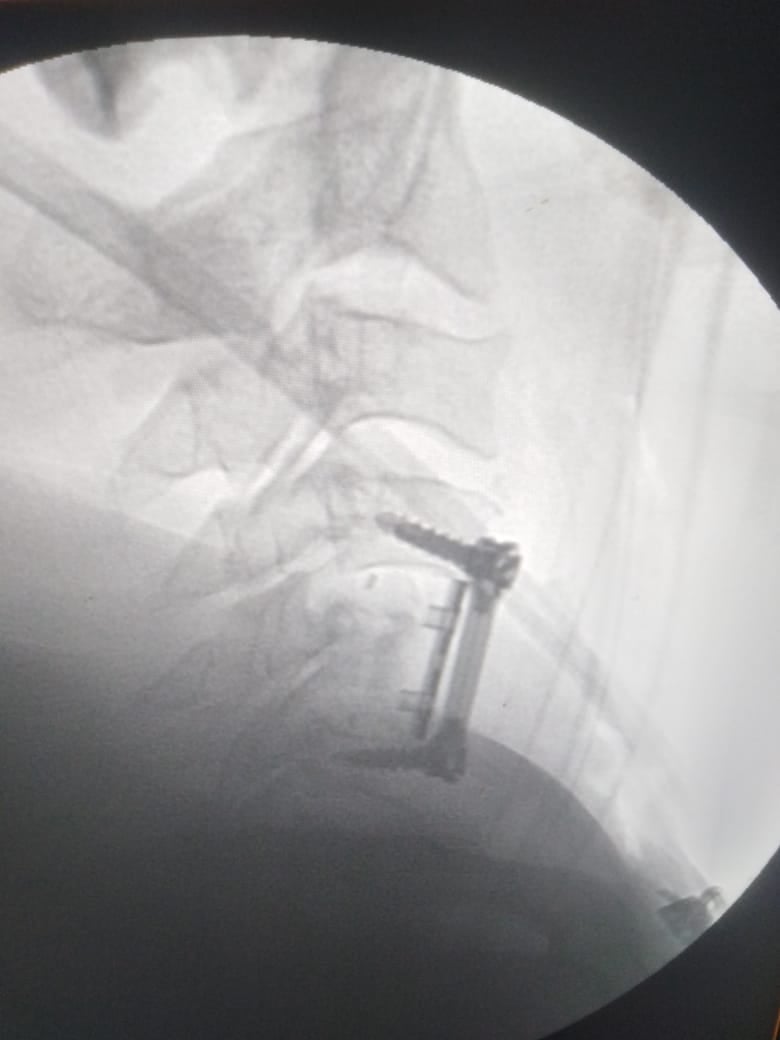

وشهدت الجراحة استئصال الفقرة الخامسة «المفتتة» ووضع دعامة عنقية وتثبيتها بواسطة شريحة ومسامير وتوسيع القناة العصبية.

وأوضح أخصائي جراحة المخ والأعصاب، أن تلك العملية تعد من العمليات الرائدة في مجال جراحات العمود الفقري في الإسكندرية، مشيرًا إلى استقرار حالة المريض عقب إجراء الجراحة، ودخوله غرفة العناية المركزة بالمستشفى تحت المتابعة المستمرة من أطباء المستشفى.